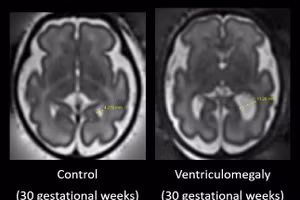

Phân biệt tự kỷ và ADHD nhờ kiểm tra mắt

GD&TĐ - Các nhà nghiên cứu cho biết đã xác định được những dấu ấn sinh học, có thể cho phép chẩn đoán, phân biệt tự kỷ và rối loạn tăng động giảm chú ý (ADHD) bằng một bài kiểm tra mắt đơn giản.